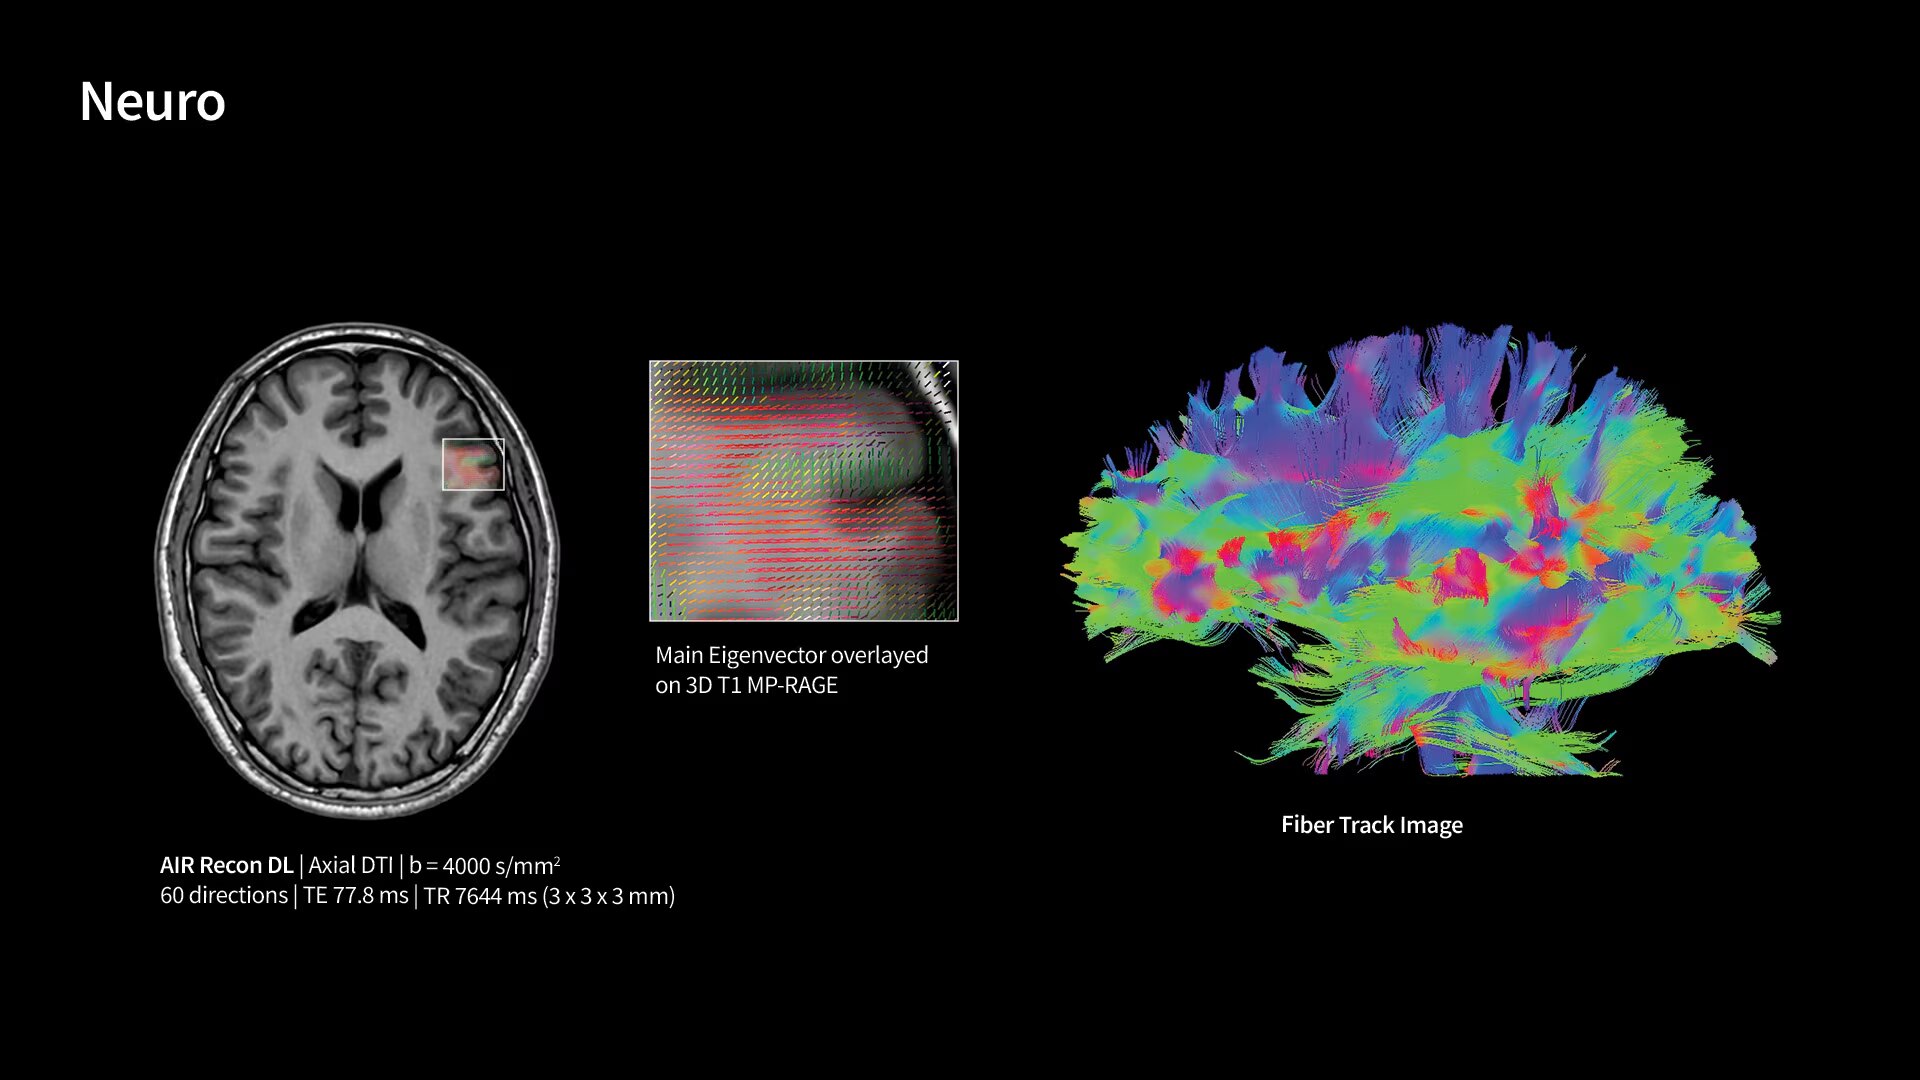

With GE HealthCare's comprehensive suite of deep-learning solutions integrated into SIGNA Sprint, you can unlock the full potential of your MRI system. No need for complicated patient setups or imaging protocols. The exceptional intelligence of our AI solutions offer multiple benefits, with AIR Recon DL giving pin-sharp images, Sonic DL accelerating scans up to 12x, and AIR x enabling automated slice placement. All helping to enhance your department’s workflow efficiency, increase patient throughput, and get the diagnostic clarity you need, faster.¹ Meaning you can spend more time on what truly matters—personalized patient care, enabling optimized treatment plans and treatment response monitoring—ultimately, supporting better clinical outcomes.